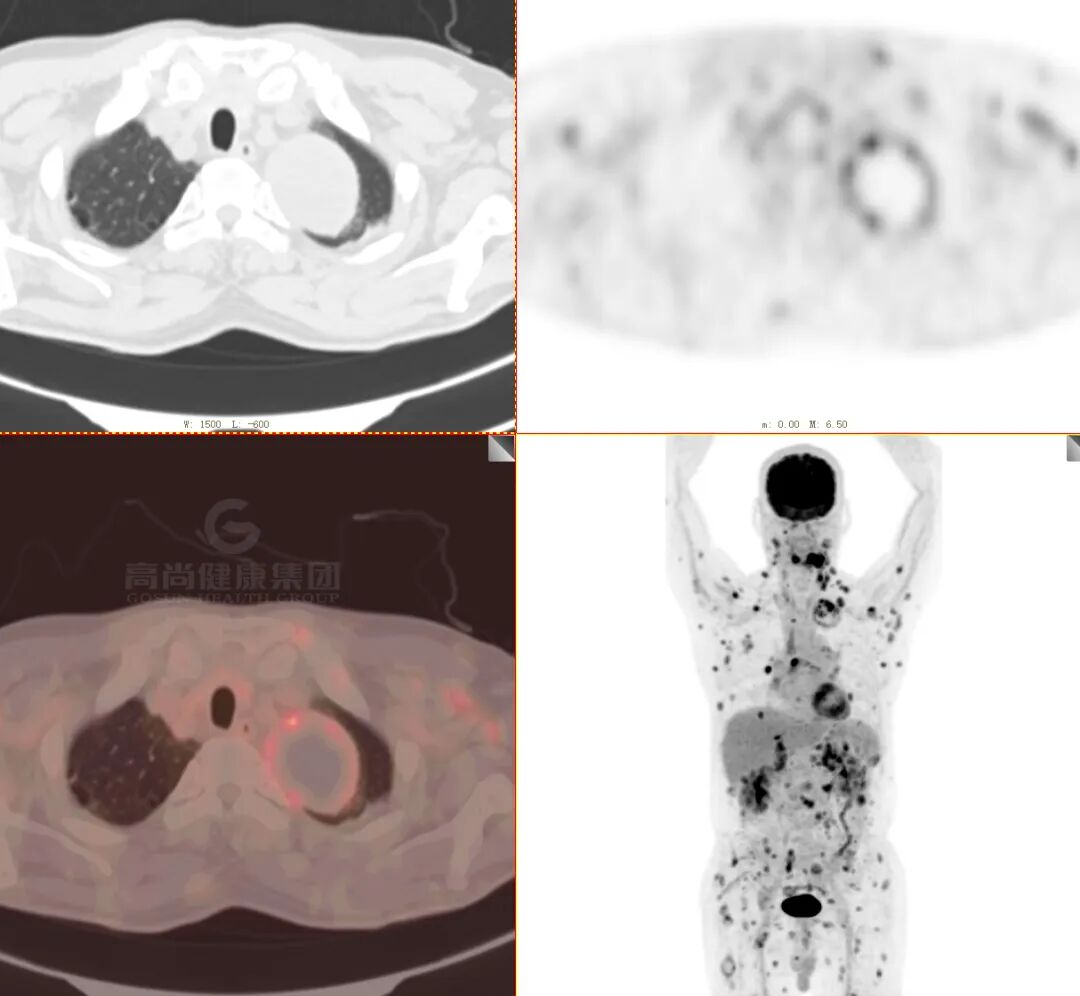

女性 69 岁,发现左肺占位 3 天。

无明显诱因出现咳嗽一周, 偶感胸前区疼痛,持续数秒可缓解,无发热。入院后行冠状动脉 CTA 检查发现左肺肿块,为进一步评估病变性质行全身 PET/CT 检查。

· 老年女性,糖尿病患者,病程短

· 影像表现重,临床症状相对轻

· 双肺多发结节、肿块,周围晕征

· 以胸膜下分布为主

· 强化较明显,未见空洞、钙化,坏死不明显

· FDG 代谢增高,SUVmax 为 18.3

(左肺下叶) 穿刺组织,其内可见纤维组织显著增生,其间散在少量肉芽肿及多核巨细胞,并见灶性坏死,可符合慢性肉芽肿性炎,未见明确恶性特征,请结合临床综合考虑。

分子靶向测序提示真菌——塔宾曲霉